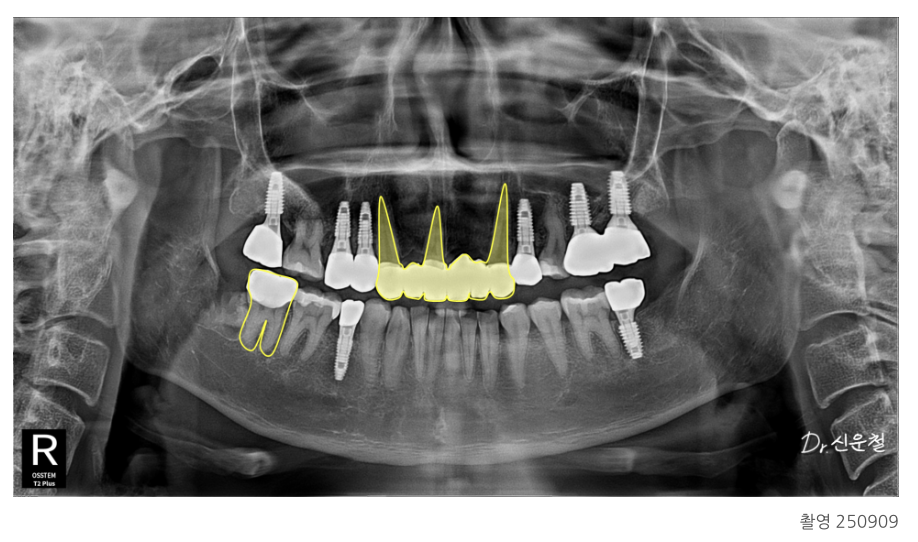

2차 치료: 남아 있는 치아는 최대한 보존

3차 치료: 임플란트 7개 단계적 식립

4차 치료: 충치 부위는 크라운, 앞니는 브릿지 보철로 자연 복원